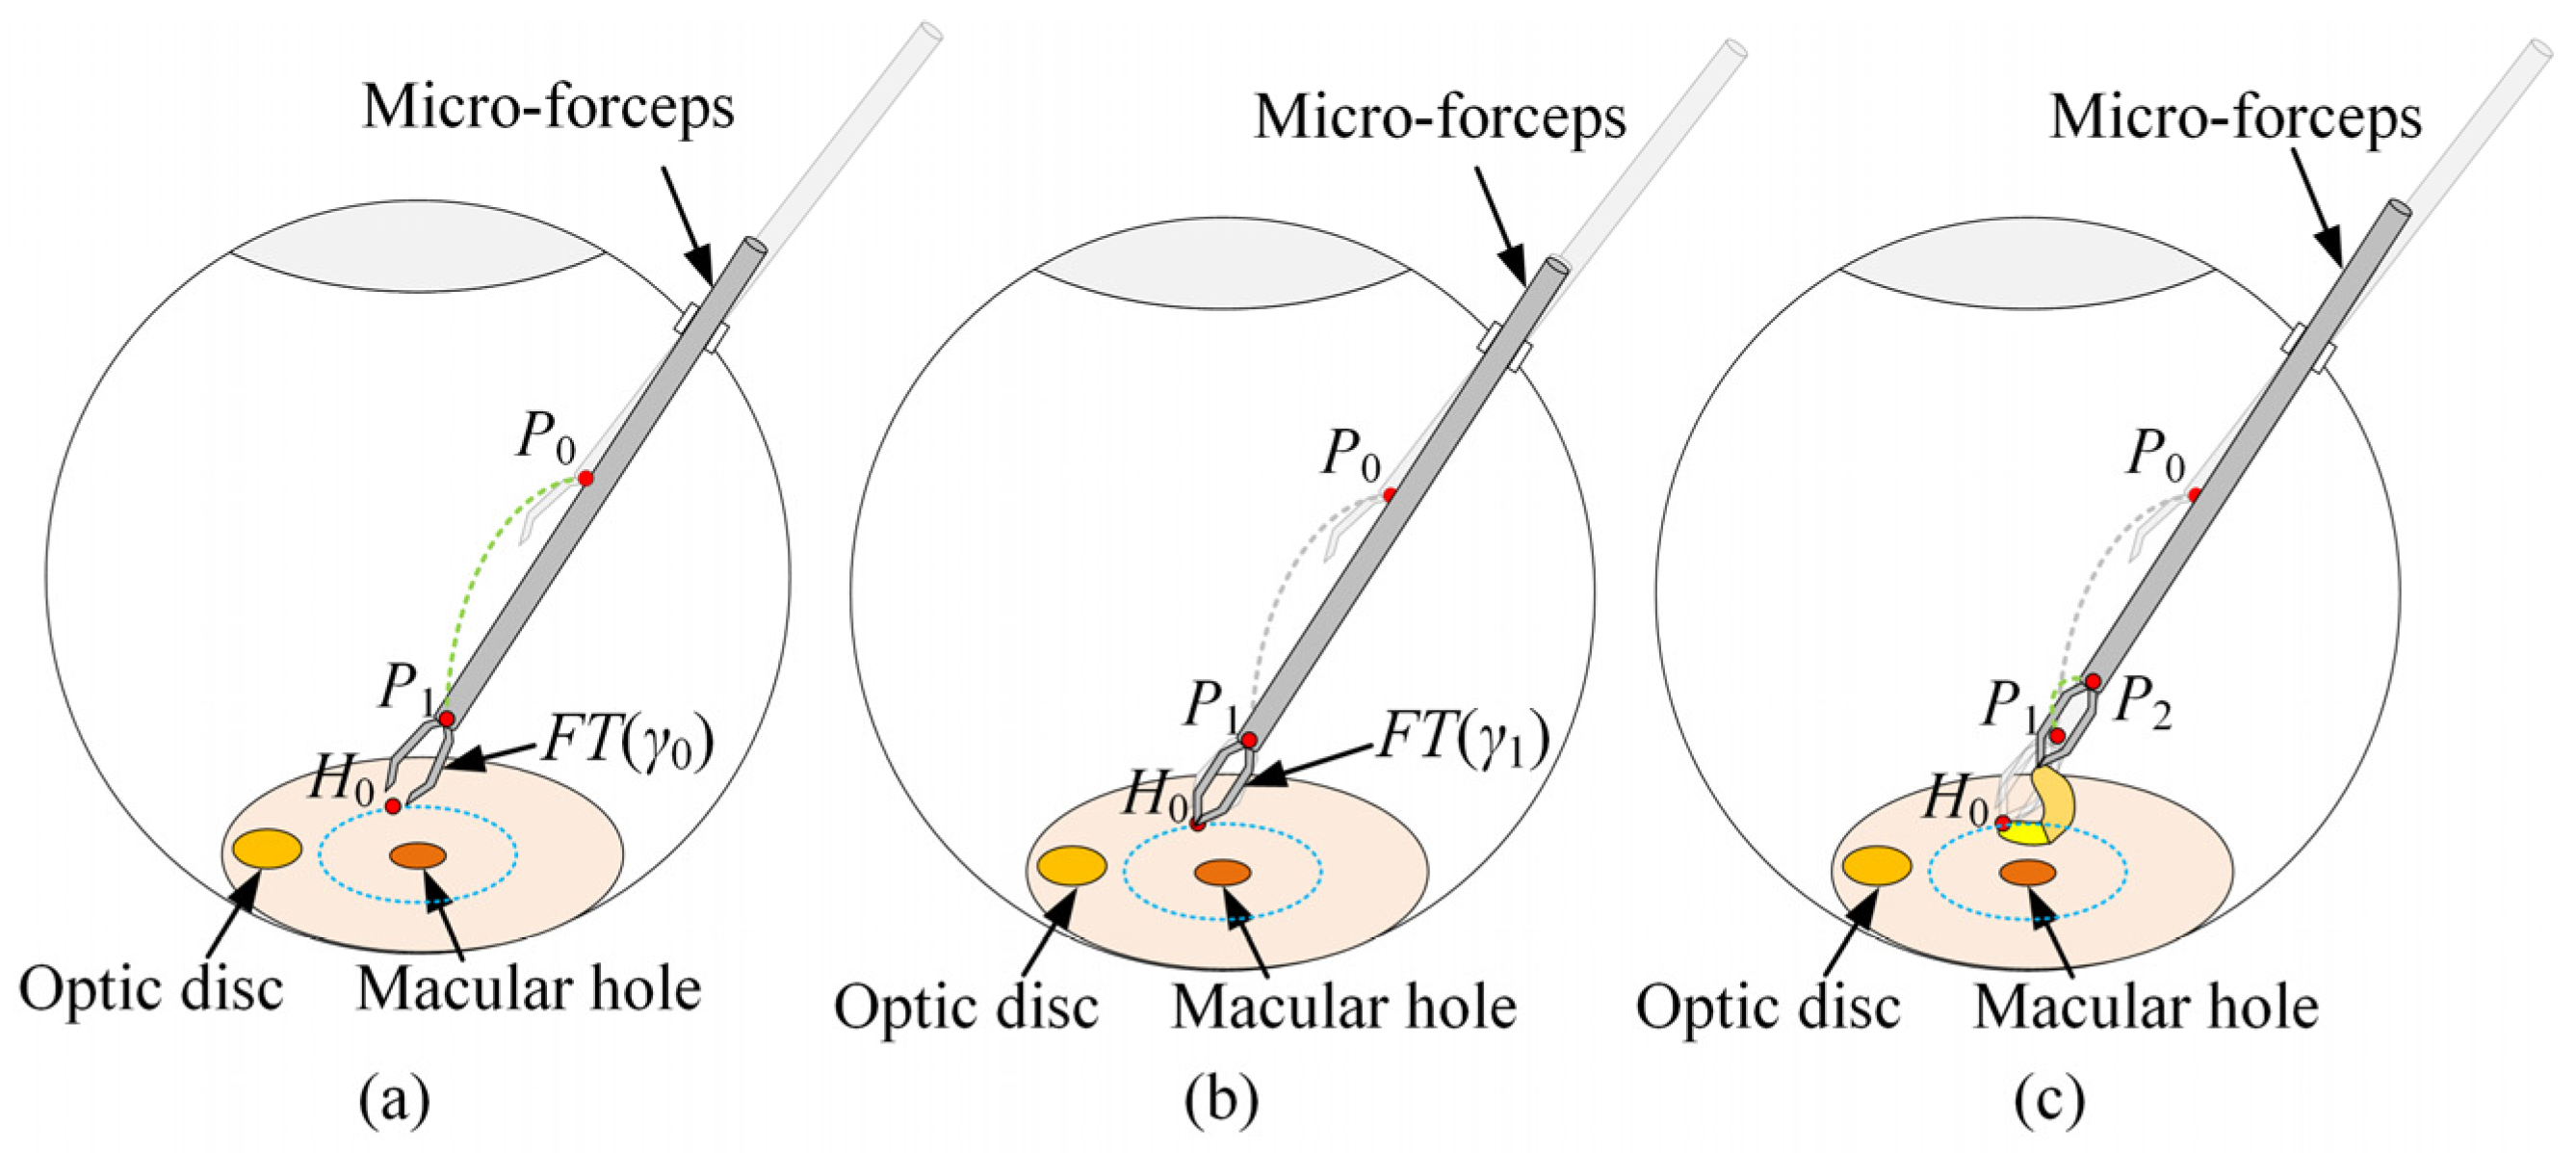

2.1. Control Framework for Automatic Break Initiation in ILM Peeling

2.4. Automatic Surgical Trajectory Planning Method